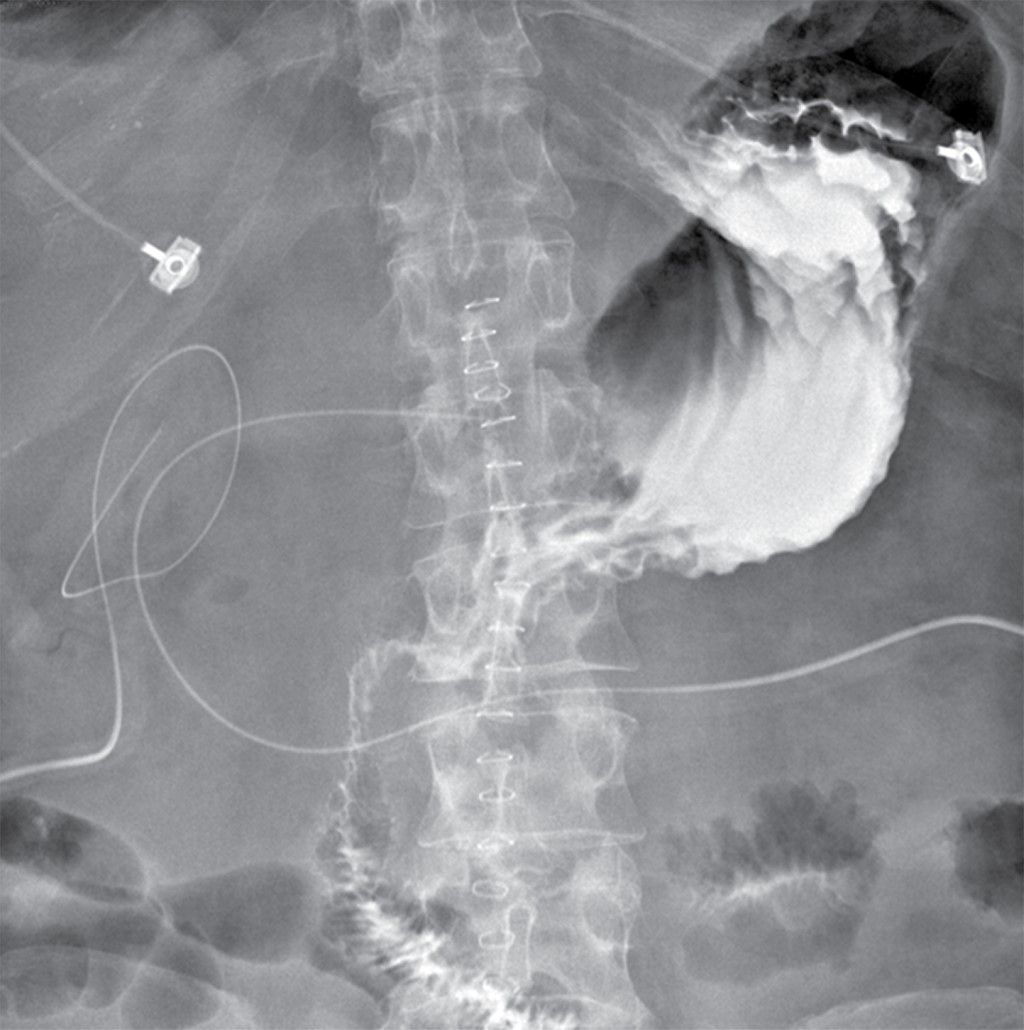

En el postoperatorio inmediato, el paciente ameritó manejo en la Unidad de Cuidados Intensivos por inestabilidad hemodinámica con mejoría paulatina en los días posteriores; retiro de ventilación mecánica invasiva y apoyo aminérgico al tercer día del postoperatorio. Se realizó serie esofagogastroduodenal en el cuarto día postquirúrgico, la cual se reportó con adecuado paso del medio de contraste hacia yeyuno sin evidencia de fuga (Figura 3). Inició la dieta por vía oral, sin complicaciones, el paciente cursaba con gasto seroso mínimo que se retiró en el quinto día postoperatorio, así como disminución progresiva de gasto por duodenostomía hasta su egreso al día siete postoperatorio, por lo que fue egresado tras su mejoría. En seguimiento ambulatorio se retiró duodenostomía en el día 23 del postoperatorio.

Figura 3